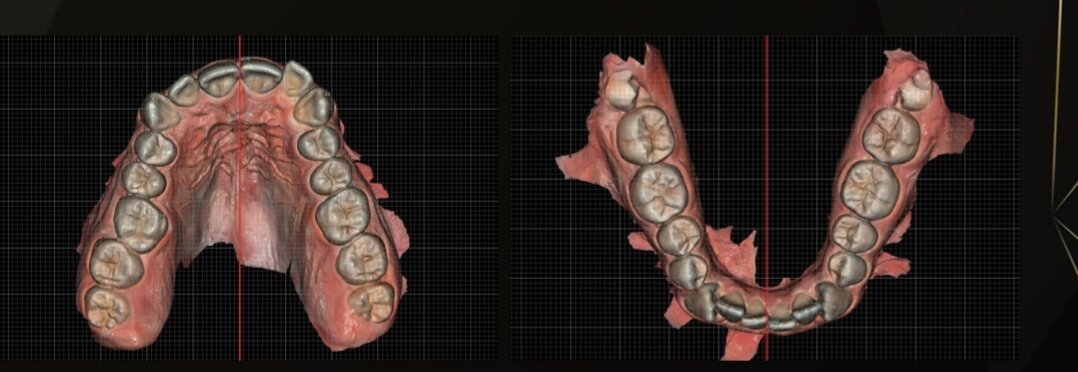

also, they don't want to expand my palate because they said its only a little bit narrow so no worth the risk (upper palate 38.5mm, lower palate 42mm).

they want to extract my wisdom teeth to create space, and they said my overbite is gonna get fixed when they align my upper teeth, because they are blocking my lower jaw (my upper teeth grew inwards).